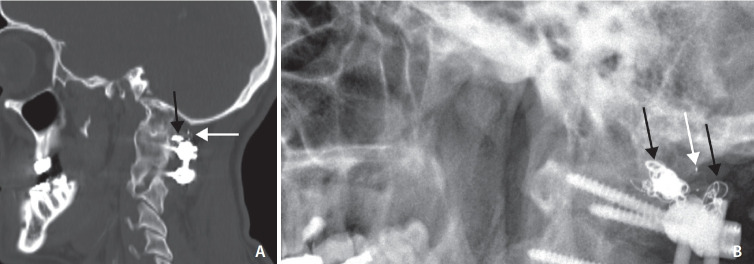

Intrasaccular Flow Disruptor (Woven EndoBridge) Assisted Embolization of Vertebral Arteriovenous Fistulas.